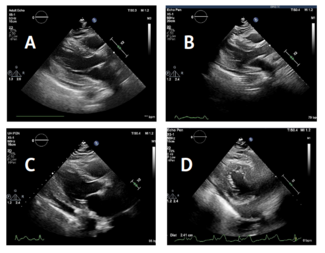

Left ventricular perforation is a rare complication of myocardial infarction, cardiac trauma, or due to an iatrogenic cause, such as cardiac catheterization, biopsy, temporary or permanent pacing, or pericardiocentesis. We present a case of a...